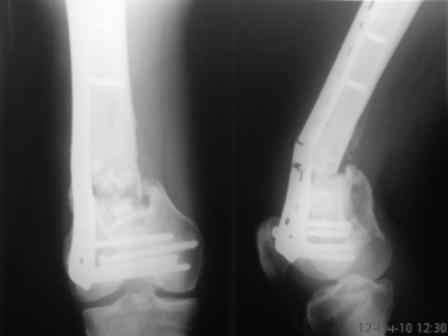

Уважаемые коллеги! Просьба поделиться соображениями в выборе дальнейшей тактики лечения. Больной, 30 лет, высокоэнергетическая травма 6 мес назад (базальный перелом шейки бедра + перелом дистального метаэпифиза бедра на той же ноге по типу 33-С2). Практически сразу же был произведен МОС шейки системой DHS (Synthes), через две недели - МОС дист.отдела бедра системой LISS (Synthes)плюс костная пластика с крыла подзвдошной кости. На сегодняшний день наступил перелом пластины, укорочение бедра 2 см. Перелом шейки клинически и рентгенологически сросся. Больной астеничен, немного анемичен. Рентгенограммы прилагаются.С уважением, Тарас Рокита, гор.больница 7, Киев